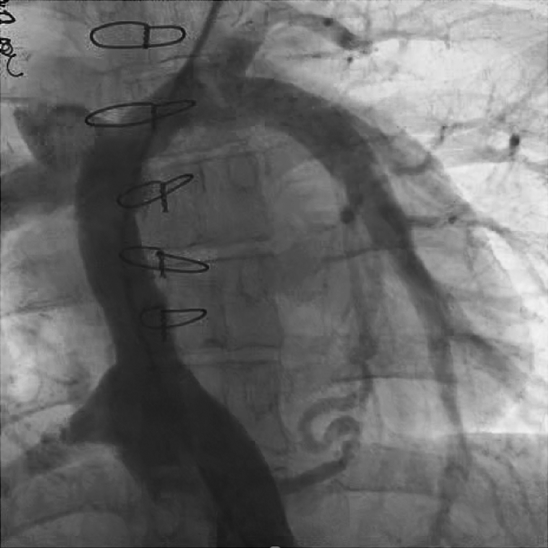

肺動脈閉鎖症,無脾症の診断で月齢3に左BTシャント変法を施行された.シャント閉塞認め,1歳3か月時に左BTシャント変法を,2歳時に右BTシャント変法を追加された.3歳時に両方向性グレン手術施行し,5歳時に心外導管型フォンタン手術(ePTFE 18 mm)施行した.術直後の心臓カテーテル検査から心外導管に造影欠損部を認めており,2 mmHgの圧較差を認めていた(Fig. 5). 17歳時の心臓カテーテル検査では,心外導管の圧較差2 mmHgと狭窄の進行はなく,下大静脈圧は14 mmHgで再手術の適応はないと判断されていた.17歳ごろより1年間ワーファリンを自己中断していた.その後当院成人先天性心疾患外来紹介.19歳時より倦怠感,下血,喀血が出現し,心臓カテーテル検査を施行した.下大静脈圧は26 mmHg,平均肺動脈圧は8 mmHgと圧較差を14 mmHg認めた(Fig. 6),心外導管に対してバルーン拡張術を施行し,下大静脈圧は20 mmHgと軽度改善したが下大静脈圧の十分な低下は得られず,手術適応と考えられ,再心外導管置換目的に当科入院となった.

Fig. 5 Angiography 4 years after Fontan completion showing an inflection in the conduit in patient 2